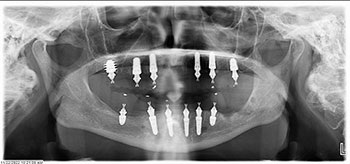

Surgery was uneventful. Extractions, site preparations and implant placements went according to plan (Fig. 3). In the maxilla, we placed six implants following the “All-on-6” concept, ensuring posterior spread for optimal load distribution. Six implants were also placed in the mandible following a similar approach.

All implants achieved excellent primary stability (>35 Ncm Torque and ISQ values averaging 72 to75), which allowed us to proceed with immediate loading (Fig. 4). Using SprintRay 3D printed provisionals in OnX Tough 2 resin, we delivered fixed temporaries the next day post-surgery (Figs. 5–8).

The patient was thrilled with her new smile and reported no pain, discomfort or issues during the three-month healing period. Regular follow-ups showed good soft tissue healing and implant integration (Fig. 9), with no signs of mobility or infection.

A surgical approach was planned for the atraumatic removal of the failed implant. We placed a Noris Medical pterygoid implant anchored in the medial pterygoid plate, achieving excellent primary stability (50 Ncm torque). The pterygoid implant allowed us to regain distal maxillary support without sinus augmentation or zygomatic implants.

To adapt the restoration to the new implant position, we used the iMetric digital verification system, capturing scans of the maxillary arch with the new pterygoid implant. A new set of provisional restorations was fabricated in-house using SprintRay OnX Tough 2 resin and immediately loaded the next day again with a screw-retained Vortex (Fig. 12).